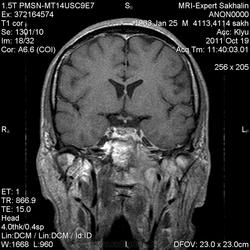

объемное образование ската с распространением на пирвмидку височной кости, область атланто-окципитального сочленения, не выраженно контрастируется- может хордома?-хотя сиггнал по Т2 для нее не типичен ( более характерен гиперинтенсивный МРС) Но ведь возможны вариации?. А КТ не делали?.

Мне тоже показалось, что хордома)))

Вы бы лучше выложили DICOM, и все срезы! А то по мелким картинкам сложно судить что-то определенное...